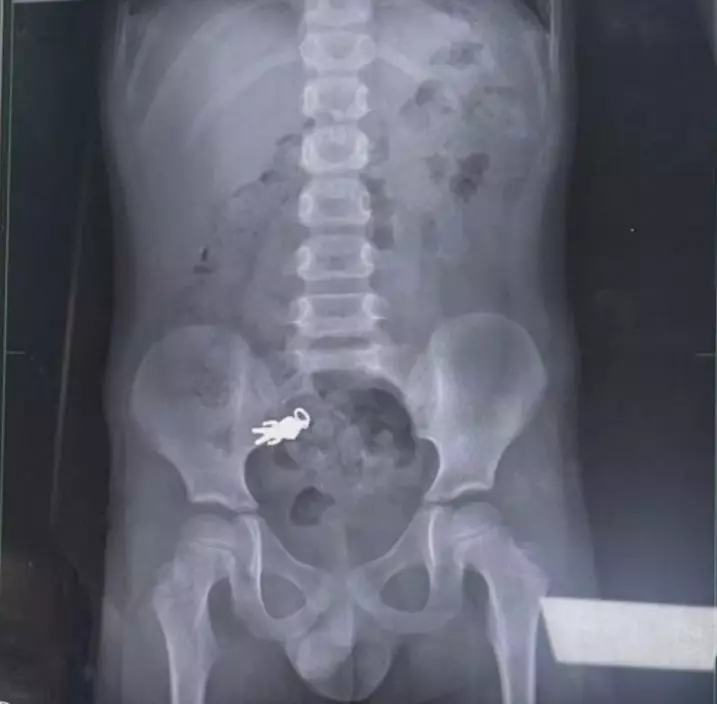

日前,台灣宜蘭一名帖主以「一邊看電視一邊吃餅乾的後果」為題社在交平台threads上發帖指出,7歲侄子在家中邊睇電視邊食餅乾時,意外將手中的「鹹蛋超人」吊飾吞落肚,之後被緊急送院治理並接受X光檢查。

X光照揭吊飾仍在體內 所幸已隨腸道蠕動排出體外

從院方拍攝的X光片中,清晰可見完整吊飾仍在男童體內,所幸最終「鹹蛋超人」已隨體內運作排出。帖主事後也更新後續笑言:「今天鹹蛋超人任務完成回來了」,並上載「鹹蛋超人」吊飾經清潔後的狀況。

醫生:吊飾大小未超危險範圍

負責個案的兒科醫生謝錦桐指出,一般而言,長度超過5釐米或寬度超過2釐米的異物,較容易於消化道中卡住,但涉事吊飾約2.8釐米乘1.4釐米,未超過危險範圍,隨腸道蠕動已進入小腸,涉事男童就醫時狀況良好,毋須接受手術,只需在家中觀察1至2日便會自行排出。